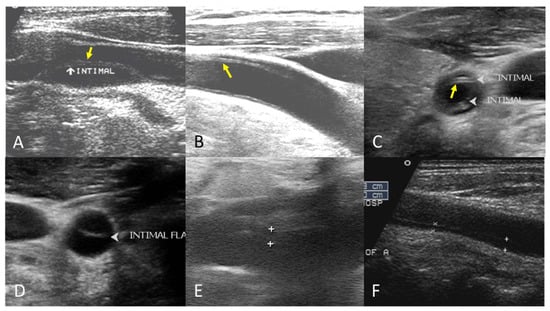

The B-mode findings of the nine CCAs revealed six typical double lumens with intimal flaps (Figure 2) and three intramural thrombi, which are also termed thrombosed false lumen (Figure 3). Supplementary Figures S1 and S2 contain the original ultrasound images. The “train-line” pattern was recognized in three of six intimal flaps and two of three intramural thrombi. The extracranial duplex sonography revealed a “train-line” pattern characterized by a thickened wall displaying hypoechoic properties, where the boundary was composed of closely placed parallel linear reflections. Patient No. 1 corresponds to Figure 2A; patient No. 2 corresponds to Figure 2B; patient No. 3 corresponds to Figure 2C,D; patient No. 4 corresponds to Figure 2E; and patient No. 5 corresponds to Figure 2F. Patient No. 6 corresponds to Figure 3A; patient No. 7 corresponds to Figure 3B; and patient No. 8 corresponds to Figure 3C. Interestingly, patient No. 5 had bilateral CCAD, but the train-line pattern was only on the right side. Figure 2C shows the right CCA with a double lumen and a clearly visible train-line pattern, and Figure 2D displays the left CCA, which also demonstrates a double lumen, but no train-line pattern is observed. Patient No. 8 presented with a hypoechoic intramural thrombus which resembled double lumens, but it was easy to distinguish under the color Doppler imaging.

Figure 2.

Double lumen with intimal flap with train-line pattern (A–C) and without train-line pattern (D–F). The ultrasound image was obtained using a 4× magnification setting. Yellow arrows indicate the “train line”. The train-line pattern is characterized by two closely positioned, hyperechoic parallel linear reflections overlying a thickened vessel wall. Symbols such as “×”, “+”, arrows, and arrowheads were generated by the ultrasound machine and used by sonographers to mark regions of interest (ROIs) where the intimal flap was located.